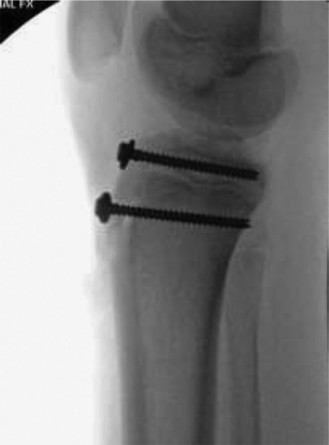

The correct answer is (D). This patient has a type III fracture, and given the amount of displacement, an open reduction is necessary. Choices A and B can be excluded because a closed reduction with casting or pinning are not sufficient treatment methods for this fracture. Given the association of type III fractures with intra-articular pathology, it is recommended to perform an arthrotomy at the time of surgery to ensure that there is no meniscal injury or soft tissue incarceration and to

ensure that the joint surface is anatomically reduced. Some advocate using arthroscopy for this purpose rather than doing a full arthrotomy—this would depend on surgeon’s preference, but regardless of technique, it is important to evaluate. Screw fixation is preferred over pins or sutures, particularly in larger adolescents because of the significant pulling force that the quadricep exerts on the tibial tubercle. In children/very young adolescents (who very rarely get this injury) you may consider suture fixation with cast augmentation if there is concern regarding the growth plates, but the injury occurs far more commonly in adolescents in whom the growth plate is already closing, so screw fixation is preferred to give more stable fixation and allow an earlier return to range of motion (Fig. 10–13).

Illustration 4 for Pediatric Cases: Optimal Closure of the Distal Femur

Clinical Radiograph / Orthopedic Image

#### Figure 10–13 Objectives: Did you learn...? What a tibial tubercle fracture is and potential risk factors? Risk of compartment syndrome with tibial tuberosity fractures?